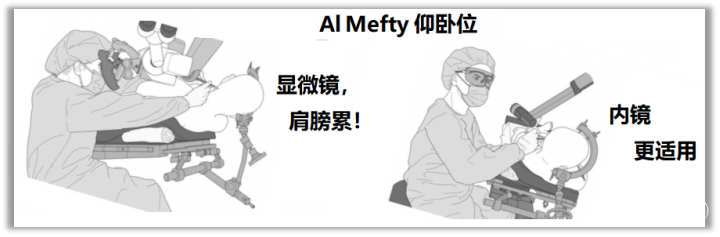

笔者推荐使用“C”弧形切口,分层切开,安全、快速、暴露充分。

弧形切口 与 直切口 优缺点对比见下图。

切口大小取决于患者颈部的长短粗细、局部肌肉厚度、可能存在的颅底骨质凹陷等畸形、术前预估手术难度等。